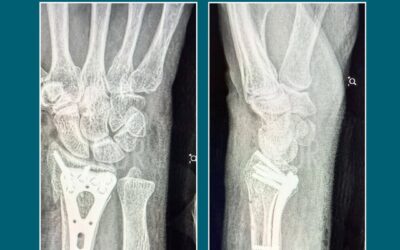

Fractura de Muñeca: Más común de lo que imaginas

En manos del Dr. Mario Dorantes Rodríguez, especialista en cirugía ortopédica, encontrarás tratamientos precisos y técnicas de fijación que restauran la función natural de tu muñeca.